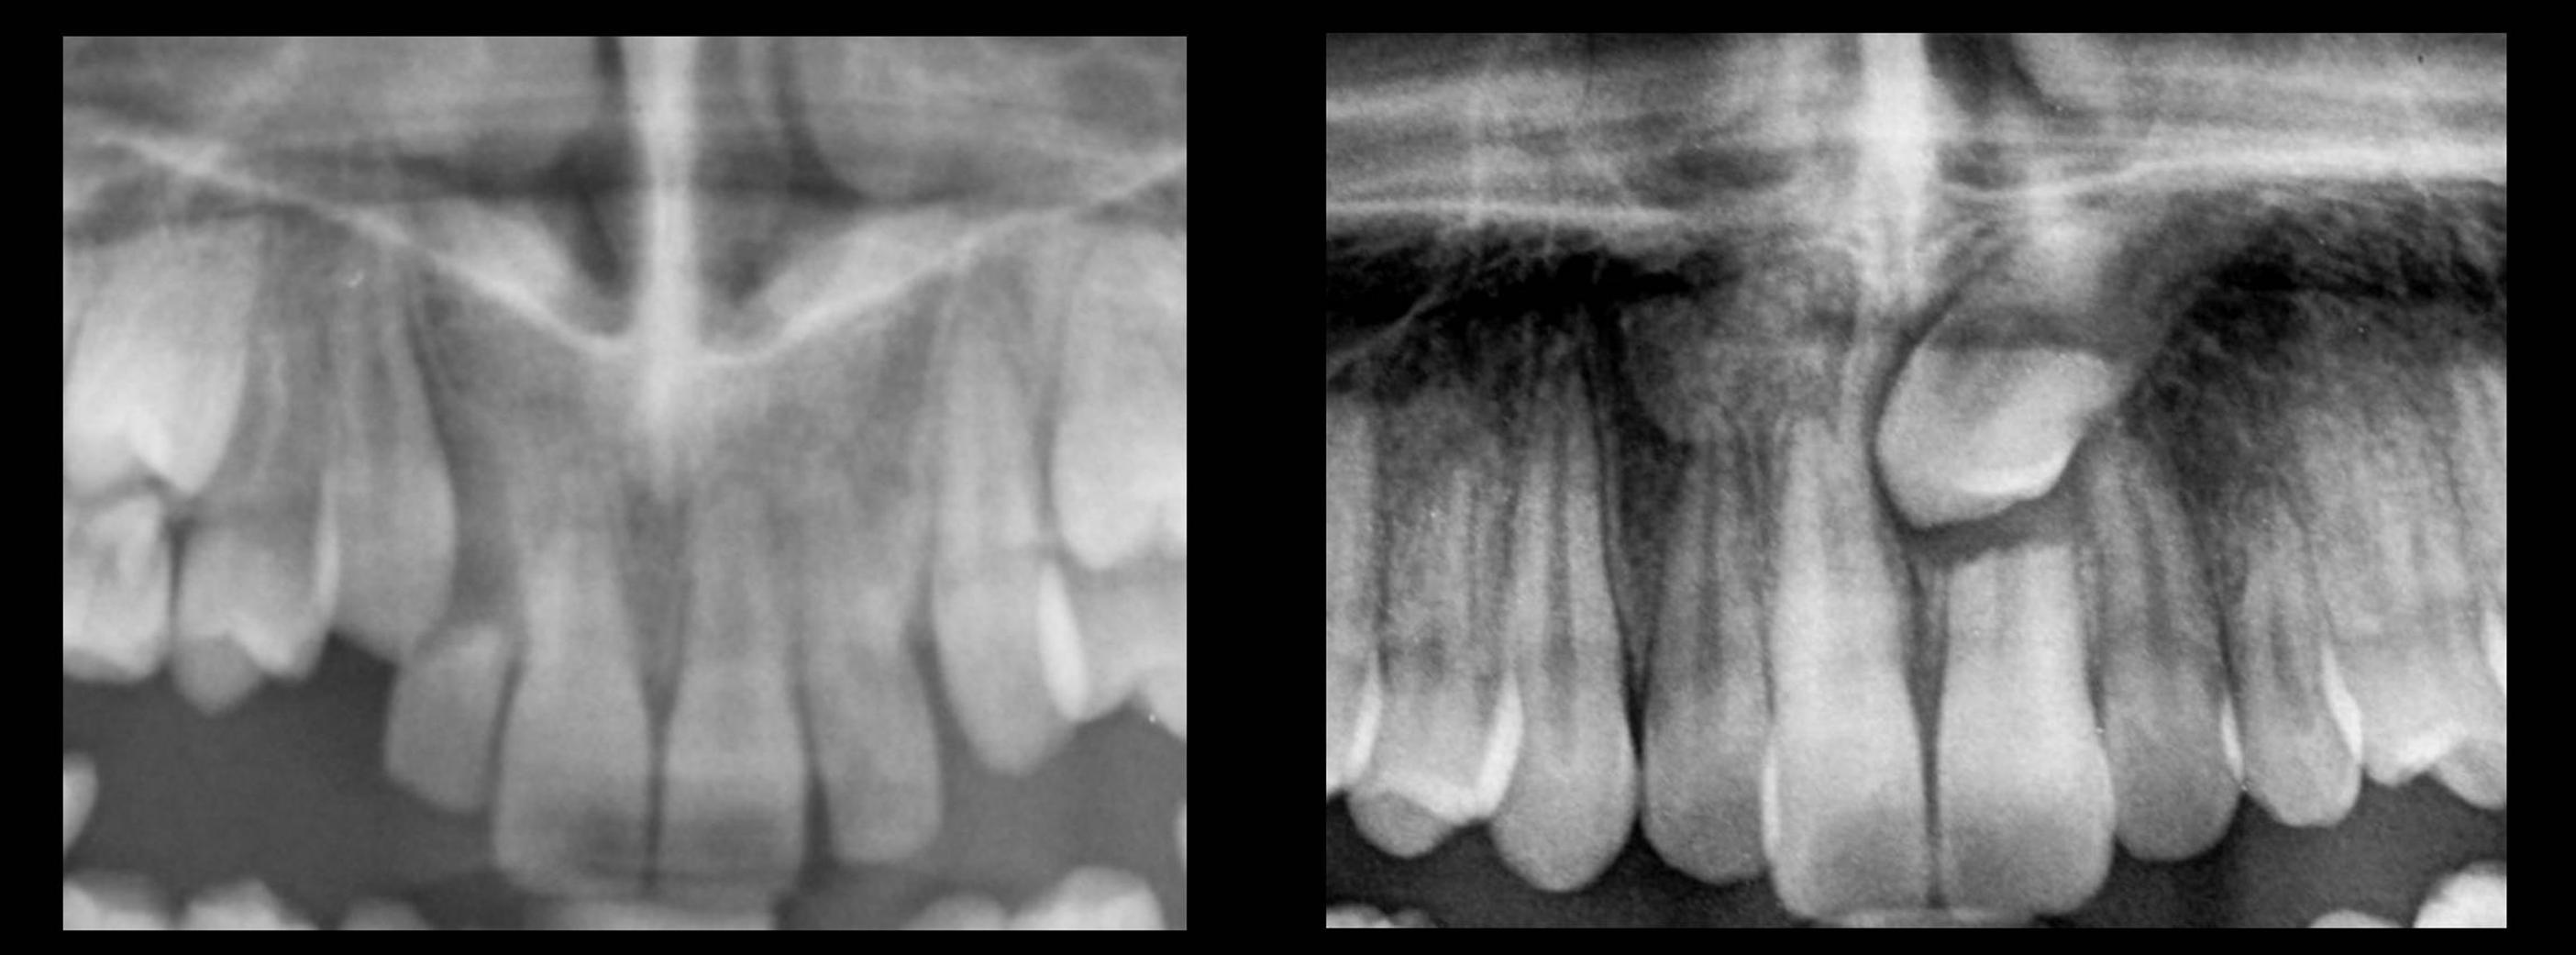

Riassorbimento radicolare degli incisivi permanenti

Il riassorbimento radicolare a carico degli incisivi permanenti � una delle complicanze pi� temibili a seguito dell�ectopia del canino mascellare. Il meccanismo per cui questo processo si instaura e i fattori che in esso risultano coinvolti non sono ben chiari, ma il fatto che si verifichi in presenza di uno stretto contatto tra la radice dell�incisivo e la corona del canino suggerisce un ruolo fondamentale di tale contiguit� anatomica5. � un fenomeno rilevante in quanto presente nel 48% delle inclusioni dei canini mascellari6. Nel 60% dei casi esso � �severo� e si accompagna a interessamento della polpa dentale, quasi sempre nella totale assenza di sintomi6. Generalmente il riassorbimento � a carico degli incisivi laterali (80%), ma talvolta anche gli incisivi centrali sono colpiti (Figura 1).

Figura

1. Riassorbimento radicolare degli incisivi.

Nell'80% dei casi il riassorbimento � a carico degli incisivi laterali, ma anche gli incisivi centrali possono esserne colpiti.

Purtroppo tale condizione patologica viene spesso sottovalutata, in quanto non sempre individuabile tramite gli esami radiografici tradizionali (ortopantomografia, radiografia endorale), specie nelle fasi iniziali, per la sovrapposizione di immagini tra il canino e la radice dell�incisivo che rende difficoltosa la definizione dei dettagli1. Ne consegue che i convenzionali metodi di indagine radiografica sono in grado di evidenziare il riassorbimento radicolare solo nel 30% dei casi, mentre la tomografia computerizzata (TC) � l�unico esame in grado di definire l�esatta entit� del riassorbimento e di evidenziarne anche quadri iniziali7,9.